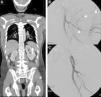

Complejo hipoperfusión-shock. Varón de 24 años. Accidente de automóvil sin cinturón de seguridad con salida del habitáculo. Signos de shock hipovolémico. TCCC con reformateos multiplanares (MPR) coronales del abdomen. A) Abdomen con hemoperitoneo (*) por estallido esplénico (flechas) e hiperrealce de ambas suprarrenales. B) MPR coronal de tórax/mediastino con lesión traumática de aorta ascendente, sin evidencia de hematoma mediastínico (flecha). C) MPR coronal de tórax/parénquima: múltiples focos de contusión pulmonar. D) Reformateo tridimensional de la pelvis: fractura de ambos fémures proximales (nótese el calibre reducido de aorta y arterias ilíacas).

Varón de 54 años con traumatismo múltiple por accidente de automóvil. Constantes vitales mantenidas. A) TCCC en fase portal, reformateo MPR coronal, que muestra laceración esplénica con pequeño hematoma periesplénico y seudoaneurisma (flecha). Fractura compleja de pelvis izquierda con focos de sangrado activo (cabeza de flecha). B) La angiografía confirma múltiples focos de sangrado activo (cabezas de flecha). C) Focos de sangrado que se resuelven tras la embolización al igual que el seudoaneurisma esplénico (no mostrado).

Imagen en el complejo hipoperfusión-shockLos hallazgos de TC pueden orientar sobre el estado hemodinámico del PTG y sobre la persistencia de hipovolemia46. El conjunto de hallazgos, denominado «complejo de hipoperfusión-shock», se caracteriza por la disminución de calibre de aorta y vena cava inferior, engrosamiento difuso e hiperrealce de la pared intestinal, disminución del realce esplénico y aumento del renal y suprarrenal, aumento del tamaño pancreático y signos de edema suprarrenal49 (fig. 3).